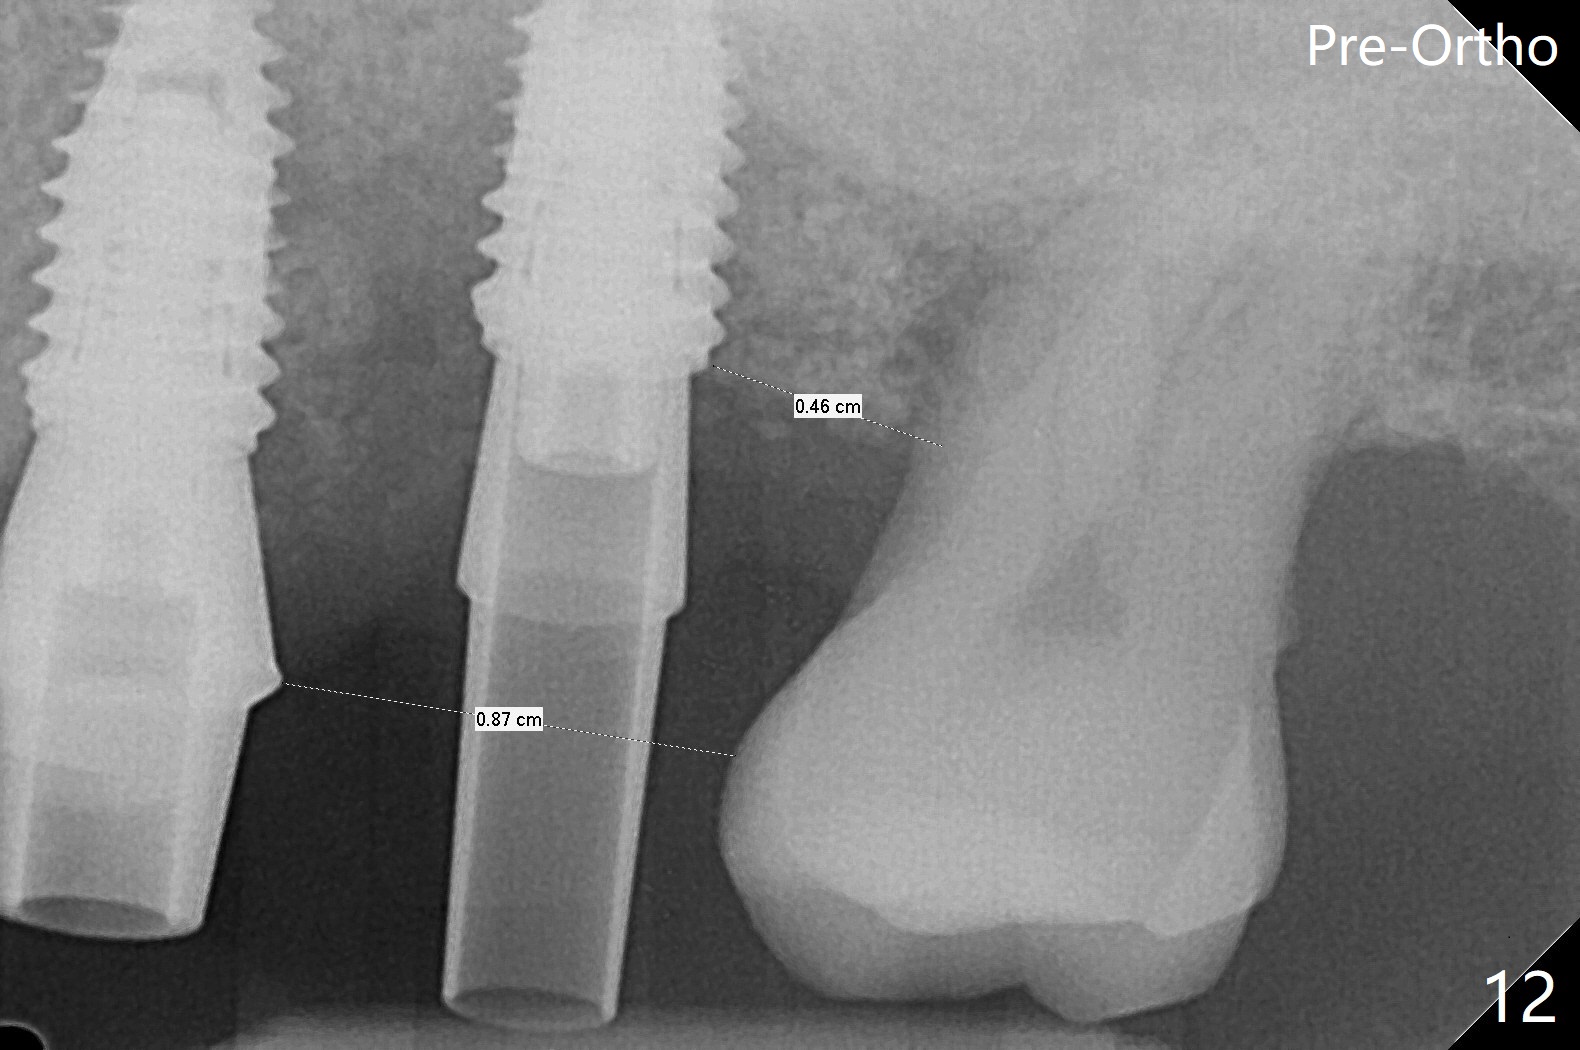

左上六植牙第三次失败后五个月,牙槽嵴宽度尚可,切开后放置导板,3.2乘19毫米园钻头好像接近上颌窦底板(图一),但是粘性骨块和4乘10毫米报废植体就不能进入上颌窦(图二),最后不得不使用3毫米Bicon骨凿,之后同一个报废植体就似乎进入上颌窦(图三),4.5乘8.5毫米正式植体植入深度和稳定性均正常(图四),腭侧植体稍微暴露,放置愈合螺丝后,放置骨粉和PRF膜,缝合,左上5植体放置5.7x4.5(4)毫米基台,固定牙周敷料。术后5.5个月植体好像整合(图五),缺牙间隙特别小,5临时牙冠(P)必须取出才能切开暴露植体,放置5.5x5毫米愈合基台(图六)。伤口愈合后,必须做渐进性负荷,之后做简单局部矫正,推7往远中,6缺失3年,7往近中倾斜移位。两周后牙周敷料脱落,伤口愈合,放置修复基台,故意将基台平面朝远中,足够空间制作临时牙冠(图七)。调整基台长度(比较图七,八)。制作连体牙冠(5,6),有意提高5牙冠高度,使左上7不与对合牙接触,有利于远中移位(图九)。也要在对侧提高咬合(图十)。局部矫正一个月后,磨去右侧咬合垫和磨短左上5,6临时牙冠,前牙还不能完全接触(图十一)。1-2星期前牙开合自行消失,取模做左上5,6牙冠。局部矫正似乎使左上7远中移位大约3毫米(比较图十二,十三)。粘固拧紧后(20 Ncm)14号牙牙冠咬合增高,拍摄根尖片(图十三),两个基台好像仍然完全就位,然后调整咬合。